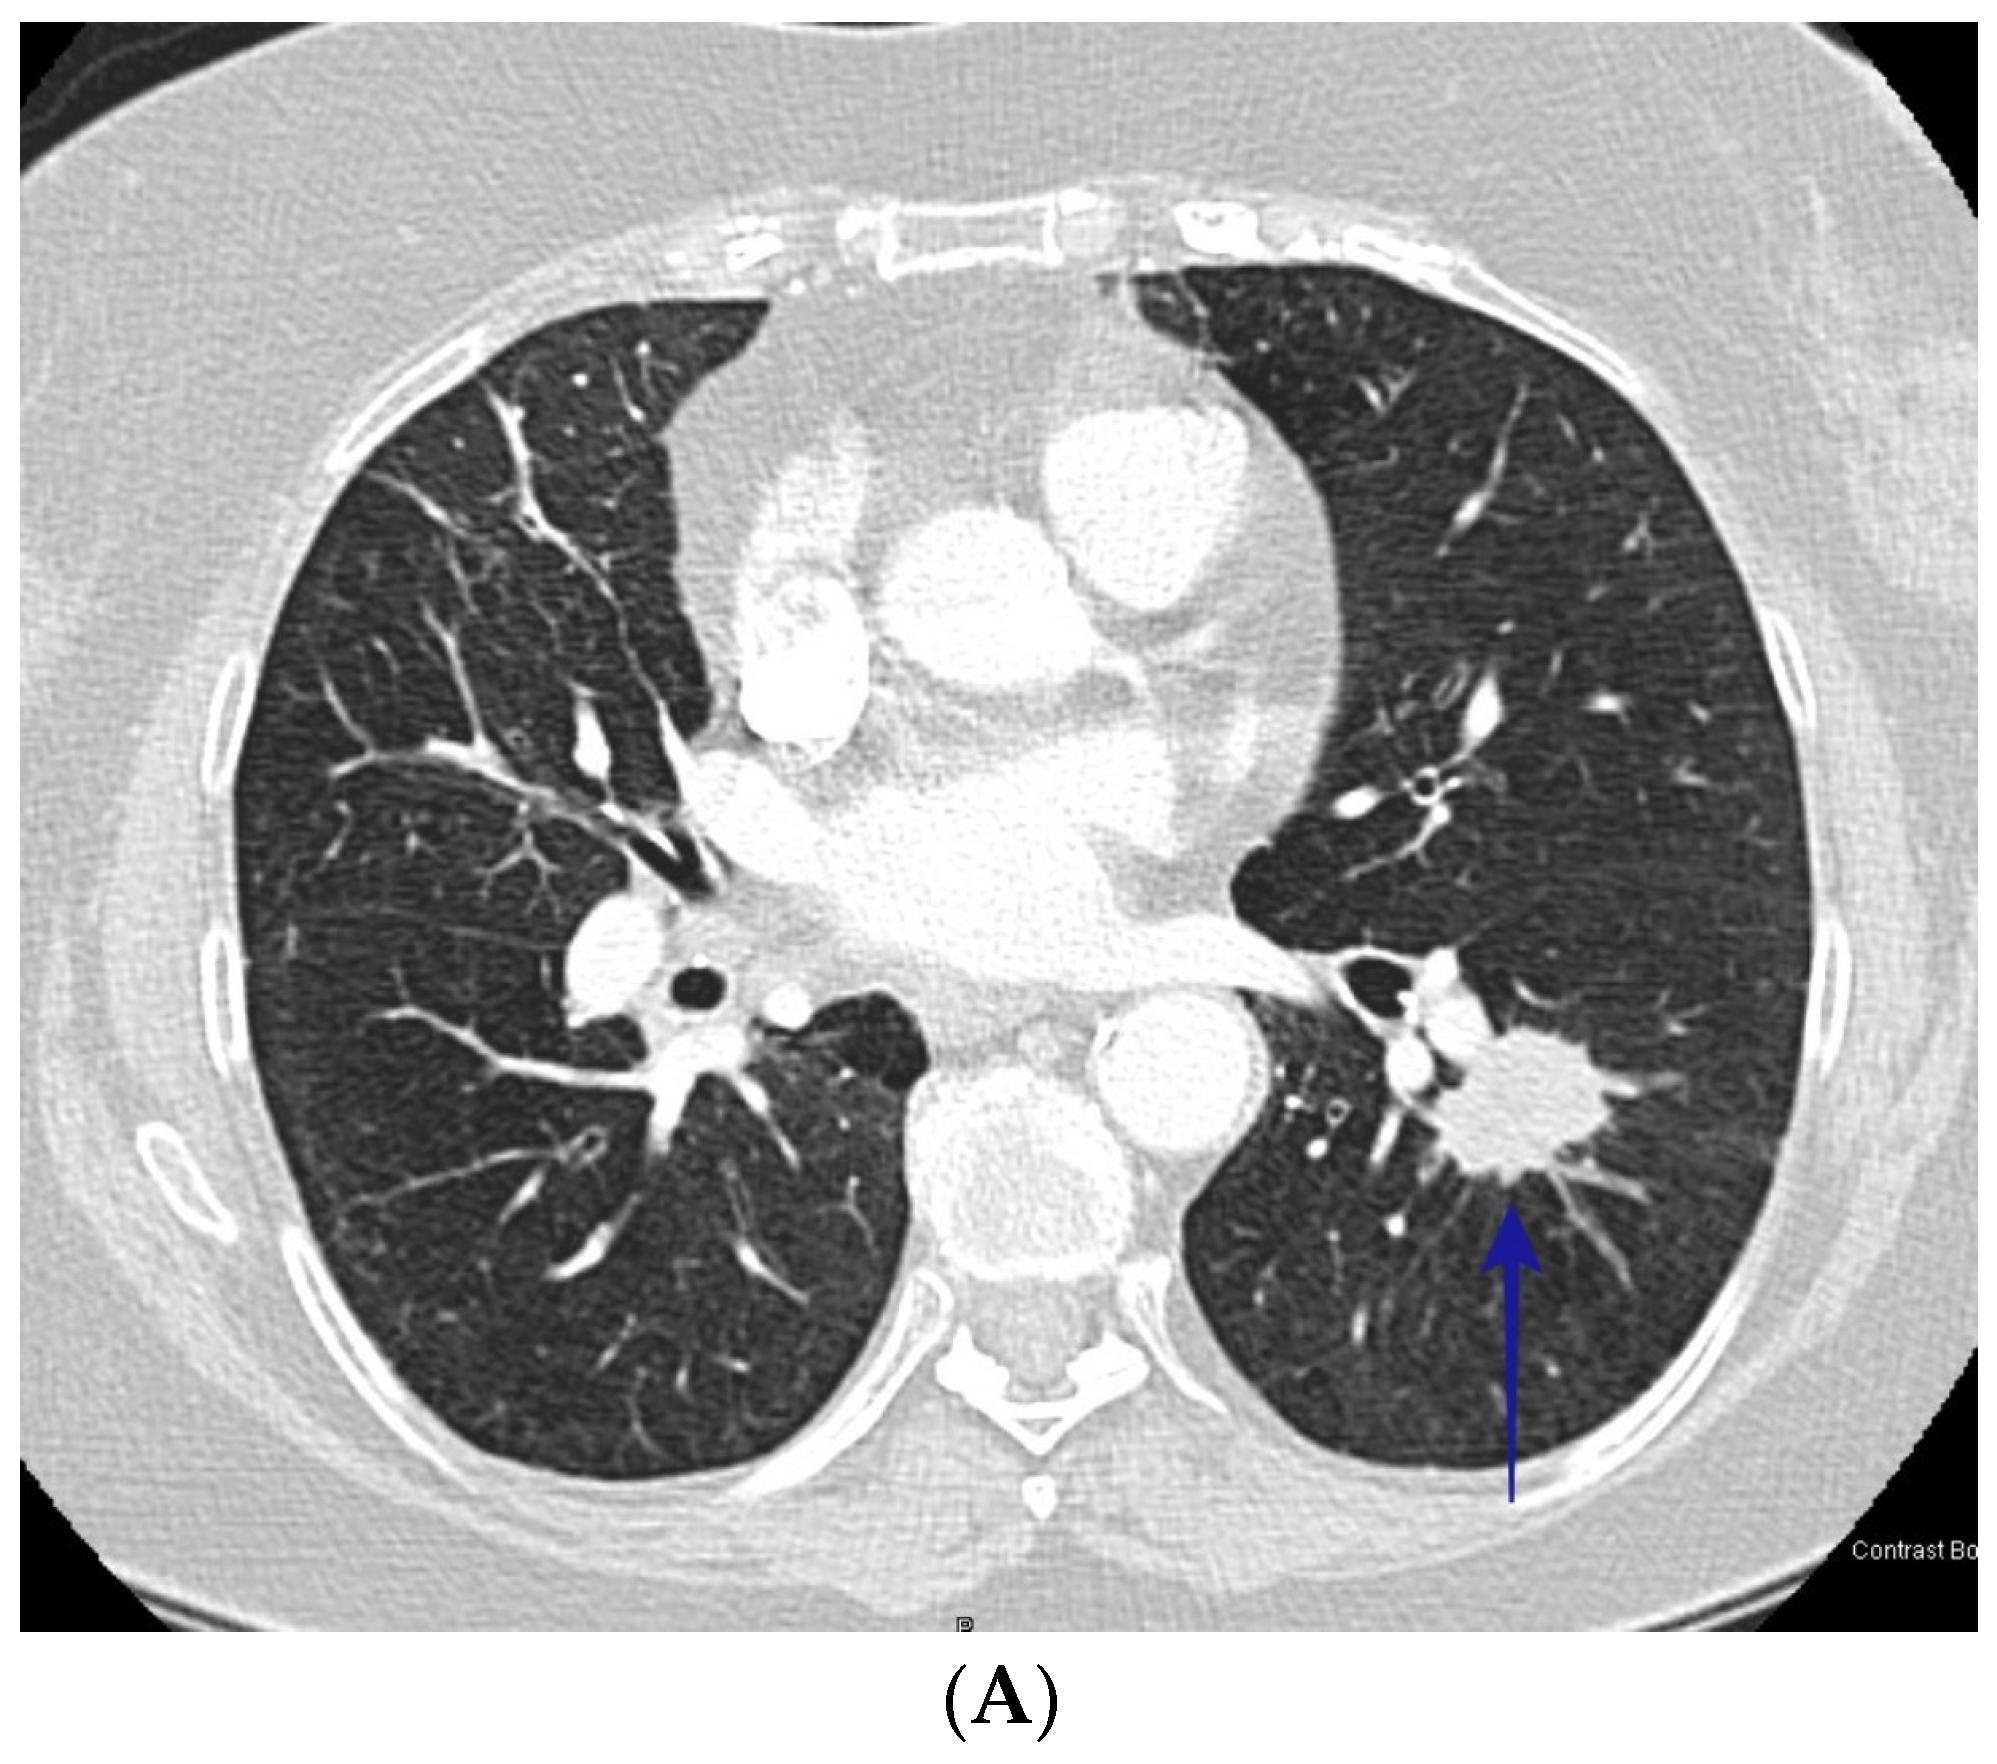

3. Results